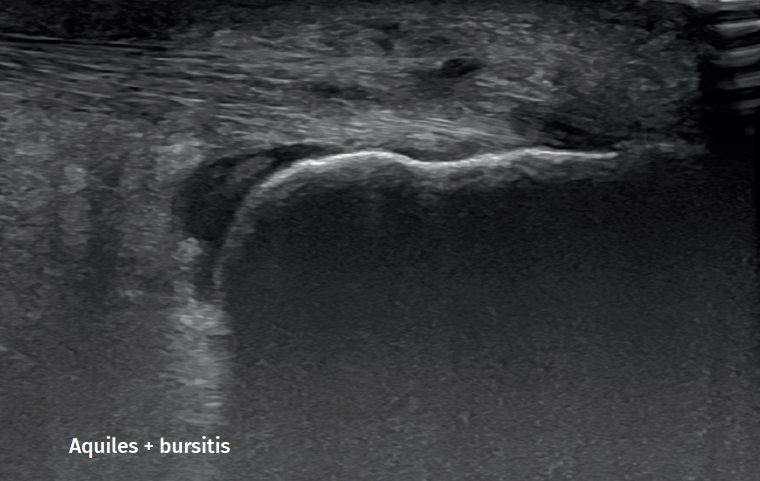

Figure 2. Retroachilleal bursitis.

However, in the chronic forms of insertional Achilles tendinopathy or enthesopathy (present in the distal 2 cm of the tendon), we can observe calcifications within the tendon in the form of traction enthesophytes or at the insertion site in the form of spurs. These conditions are often associated to alterations of the retroachilleal bursa(5,31)(Figure 2).

Retrocalcaneal bursitis is characterized by an increased volume of the bursa, with the possible association of Haglund deformity(25). In the case of retroachilles or superficial calcaneal bursitis we can identify fluid between the skin and the Achilles tendon(5).

Retrocalcaneal bursitis is in turn characterized by hyperintense images in T2 sequencing in the retrocalcaneal recess(5), while in retroachilles bursitis or superficial calcaneal bursitis, inflammation of the bursa results in hyperintense images in T2 sequencing(5).